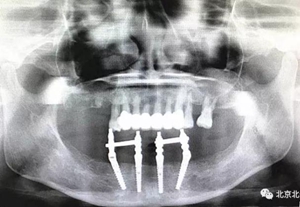

圖二十二:2015年到2016年復(fù)查時(shí)X片 ,有圖有真相

沒有假貨,貨真價(jià)實(shí),完成三年復(fù)查。

圖二十四:2017年11月復(fù)查時(shí)照片,植體很穩(wěn)定, 無骨吸收。